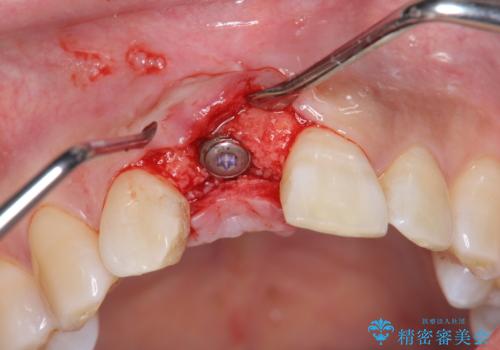

審美的・機能的に良好な位置に埋入するには、骨量が十分ではなかったため骨の造成を併用したインプラント埋入外科手術を行います。

前歯のインプラントを審美的に仕上げるには、インプラント周囲に十分な骨の量と厚みのある歯肉、そして埋入位置の精密な位置付けが重要です。